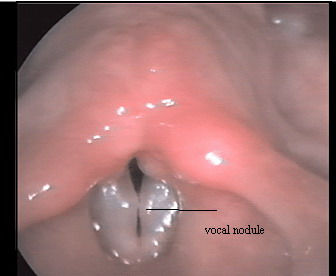

Image showing bilateral vocal nodule

This disorder frequently affects children and adults. In children it appears as spindle shaped thickenings of the edges of the vocal cords, whereas in adults they appear as more localised thickenings, varying from small points - nodules. These nodules typically appear at the junction of the anterior and middle 1/3 of the vocal cords. They appear almost aways symmetrically.

These stages can be clearly observed by laryngoscopy under stroboscopic light. Local oedematous swelling of recent onset vibrates in phase with the whole vocal fold, whereas an older and more fibrous swelling can impede the vibrations so much that only a part of the cord is seen to vibrate. The improvement in the vibration pattern or signs of recovery are picked up early during stroboscopic examination.